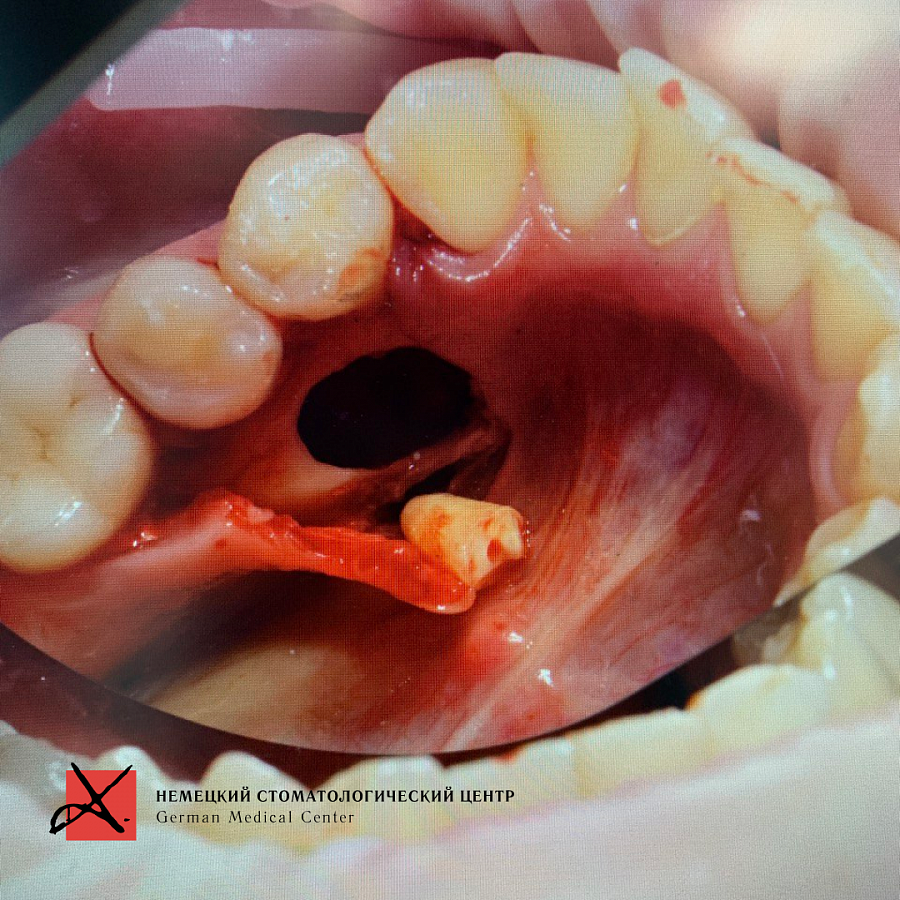

Пациент направлен врачом-ортодонтом с целью удаления ретинированных дистопированных зубов. У пациента аномалия: лишние зубы в передне-боковых отделах.

Зубы были удалены через окошко в кости, сделанное изнутри полости рта со стороны языка. Заживление прошло отлично, пациент ни на что не жалуется, соседние зубы не были повреждены.